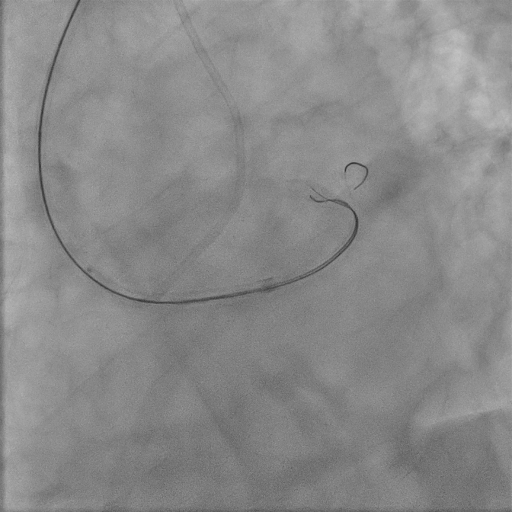

We used 7Fr EBU 3.5 guiding catheter to provide strong support, with diagnostic JR4 as contralateral injection. We started with antegrade wiring, which turned out to be difficult. There seemed to be a little bit of stump in the proximal cap but wire manipulation towards the stump was difficult, owing to the bending angle right at left main trifurcation as well as presence of calcium nodule in ostial stent. We failed proximal cap puncture despite escalating to Conquest Pro 12 loaded in single lumen microcatheter (SLC), which often backed off upon wire probing. Balloon assisted power puncture failed as well. To overcome the acute bending hindering wiring force exertion, we switched to an angulated microcatheter SuperCross120. By this manouvre we were able to advance our wire slightly into very proximal part of LAD stent, but it was deviated from central lumen and we failed to track down SLC. Hence we switched to parallel wire technique with use of a dual lumen microcatheter. The 2nd wire was able to reach the distal part of the stent only despite switching back to SLC and 1.0 balloon dilatation. Our next step was using the 0.9mm laser catheter to perform calcium modification within the ISR segment sequentially with saline, blood and contrast medium. After this manouvre, LAD was finally successfully wired with Fielder XTA, followed by balloon dilatation under IVUS guidance. Balloon expansion in ISR was suboptimal, hence it was treated with shockwave and drug coated balloon.

Final angiogram.avi